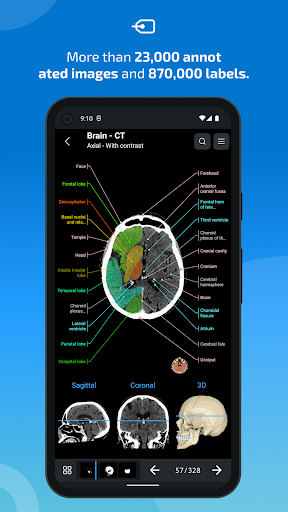

e-Anatomy tiene más de 26 000 imágenes que contienen series de imágenes en vistas axiales, coronales y sagitales, así como radiografías, angiografías, imágenes de disección, gráficos anatómicos e ilustraciones. Todas las imágenes médicas fueron etiquetadas cuidadosamente, más de 967 000 etiquetas disponibles en 12 idiomas, incluida la Terminologia Anatomica latina.

- Toque las etiquetas para mostrar las estructuras anatómicas

- Seleccione las etiquetas anatómicas por categoría

- Localice fácilmente las estructuras anatómicas gracias a la búsqueda de índice